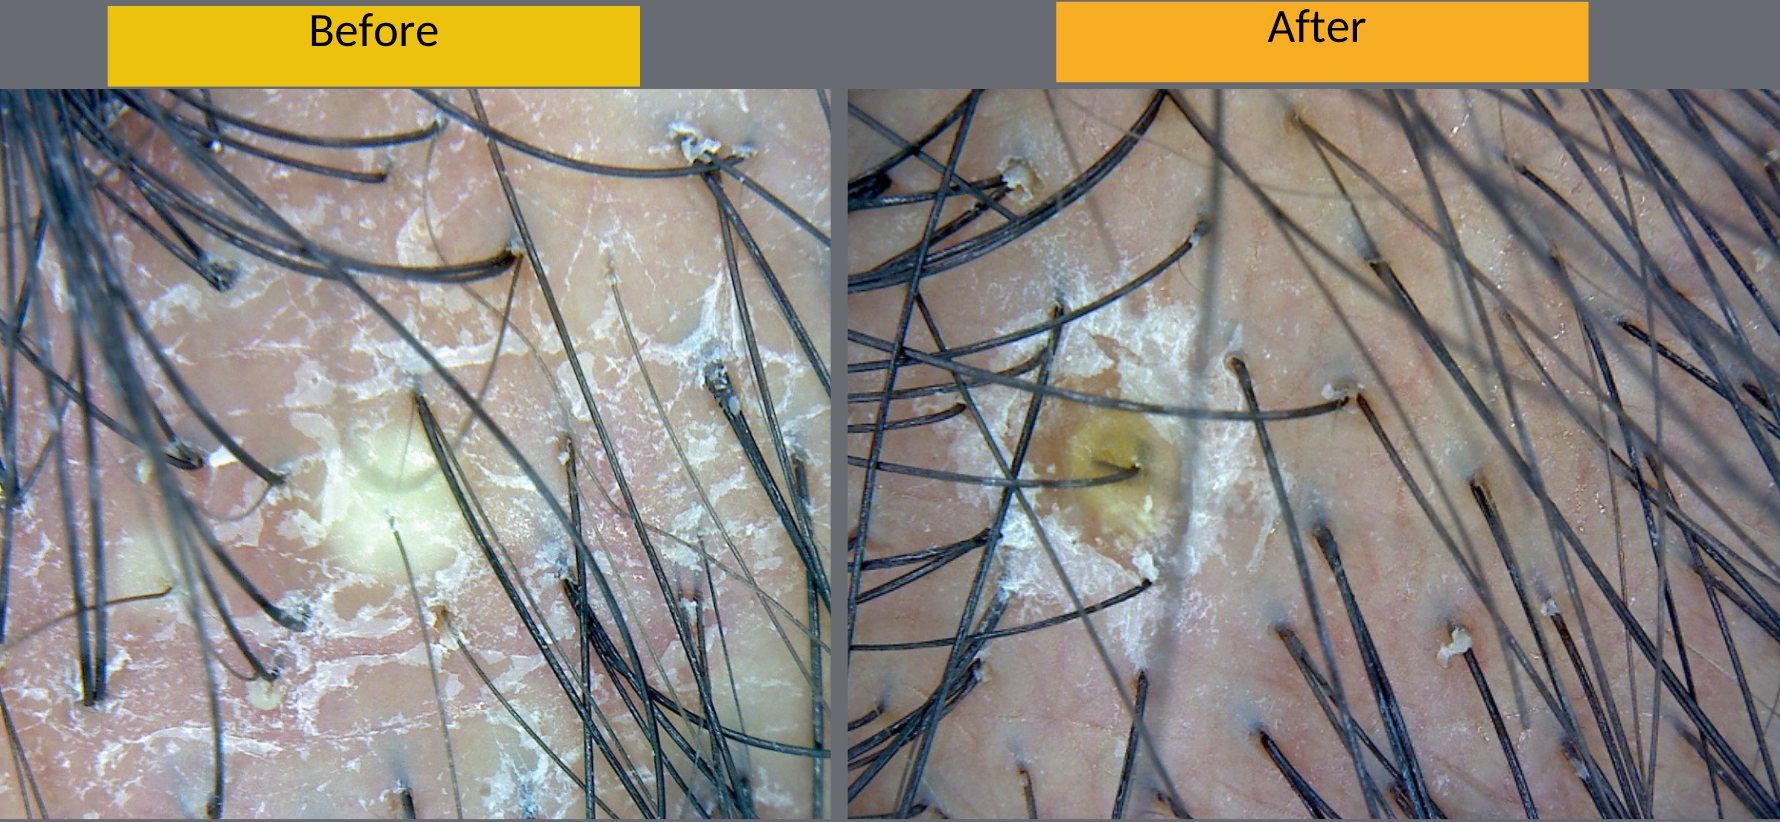

✔ Chronic dandruff (Seborrhea capitis)

✔ Scalp folliculitis (boils, infections)

Scalp exam with trichoscopy

Identify boils with trichoscopy